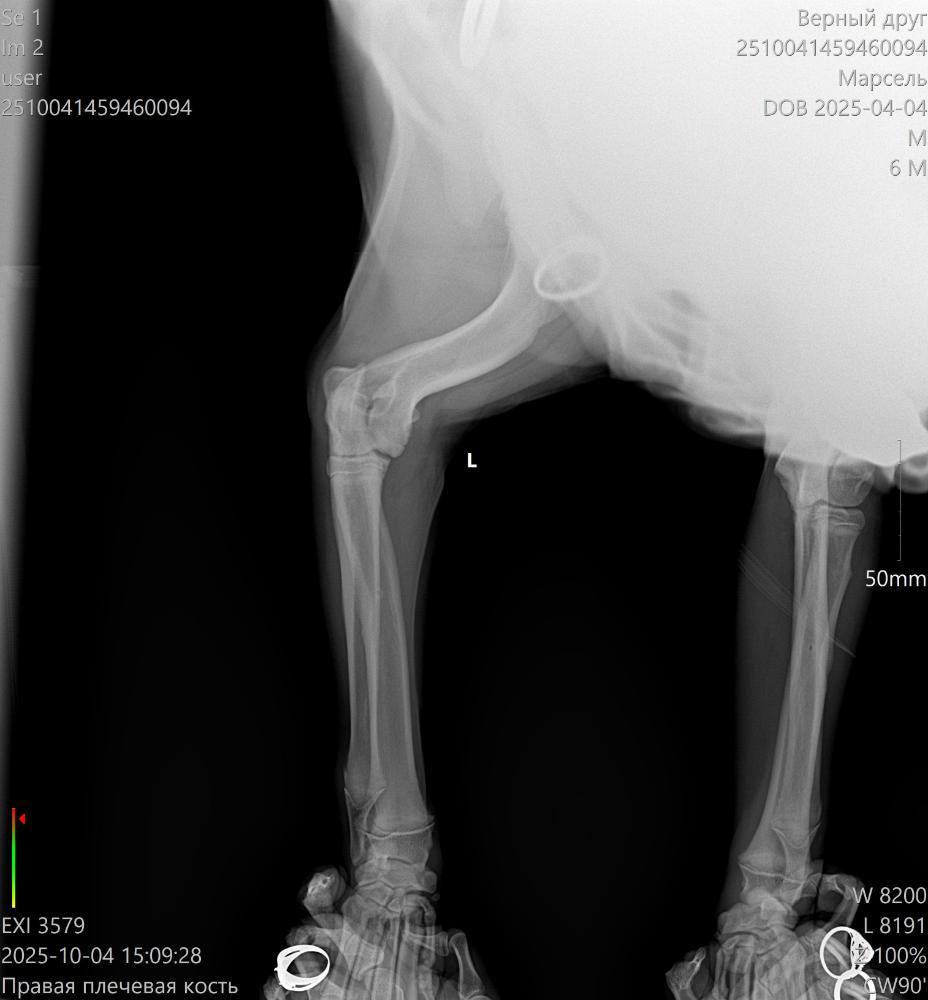

Здравствуйте. Щенок 6,5 месяцев начал периодически хромать на правую лапу. Сначала думали, что может ушиб или потянул лапу, съездили в клинику, нас отправили к ортопеду. Сходили к нему и сделали ренген и КТ. По результатам КТ: "Заключение: 1. Признаки РОХа (расслаивающий остеохондрит) в структуре медиальных надмыщелков плечевых костей обоих локтевых суставов (в правом локтевом суставе выражено в большей степени)."

После КТ были у 2 ортопедов. Один говорит, что нужно срочно делать операцию, второй выписал таблетки и сказал понаблюдать пару месяцев. Подскажите, пожалуйста, может кто-то сталкивался с таким заболеванием? Что лучше - подождать и понаблюдать или делать операцию? Если ждать, то не упустим ли время, а если делать операцию, то щенок еще растет, как это скажется на растущем организме?

2510041459460094_Марсель__04-10-2025 15_09_28_1-2.jpg